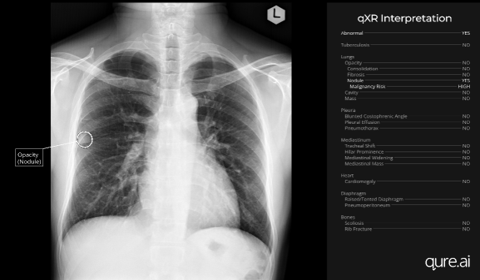

The super User Training Program will have a critical focus on understanding how AI tools are integrated into the existing radiology workflows, including their intended use, strengths, and constraints. Participants will also engage with the regulatory and ethical frameworks governing AI deployment, alongside protocols for clinical review and post-market surveillance. The importance of patient and public involvement in AI-driven initiatives will be highlighted. The program will also include a practical demonstration of the deployed system in a clinical setting.